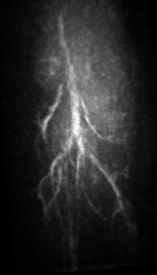

V.3 Experimental results

The maximum intensity projection (MIP) of the 3D mouse images reconstructed by use of the GPU-based implementations reveal the mouse body vasculature as shown in Fig. 7. Images reconstructed by use of both the PLS-Int and the PLS-Sph algorithms appear to have cleaner background than do the images reconstructed by use of the FBP algorithm from the same amount of data. All images reconstructed by iterative algorithms were obtained by 202020-iterations starting with uniform zeros as the initial guess. The PLS-Int algorithm took approximately a half day and 222 days to process the “quarter data” and the “full data” respectively. The PLS-Sph algorithm took approximately one day and 444 days to process the “quarter data” and the “full data” respectively. Alternatively, if the CPU-based implementations were utilized, the PLS-Int algorithm would take an estimated 686868 days and 277277277 days to process the “quarter data” and the “full data” respectively. The PLS-Sph algorithm would take an estimated 275275275 days and 1,10011001,100 days to process the “quarter data” and the “full data” respectively.